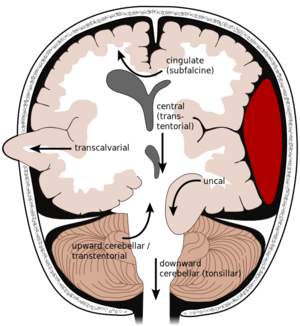

مرض وعائي دماغي

| مرض وعائي دماغي Cerebrovascular disease | |

| Cerebral angiogram of a carotid-cavernous fistula | |

| التخصص | طب القلب, طب الجهاز العصبي |

| الأنواع | Stroke, Vascular dementia, TIA and Subarachnoid haemorrhage [1] |